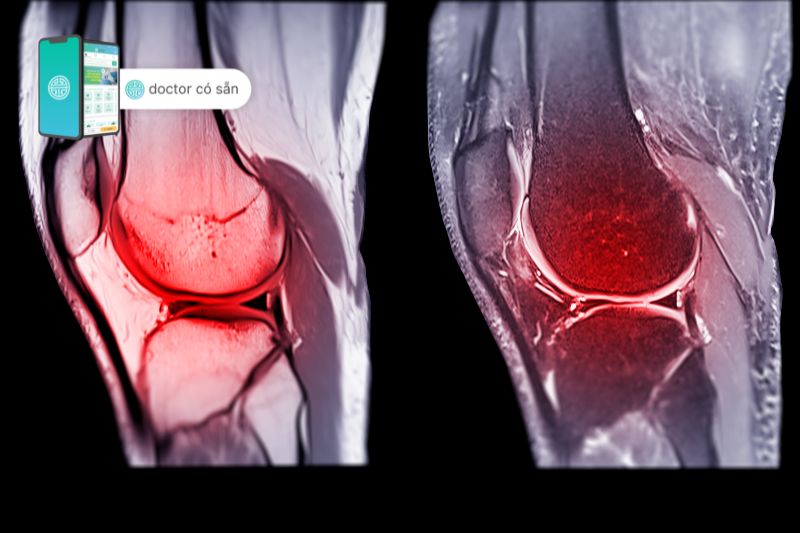

Dây chằng chéo trước (ACL), một trong những dây chằng thường bị tổn thương nhất ở đầu gối, chạy chéo qua giữa khớp. Khoảng một nửa số chấn thương ACL còn kèm theo tổn thương sụn chêm, sụn, xương hoặc các dây chằng khác ở đầu gối, làm phức tạp quá trình lành vết thương. Sau khi điều trị sơ cứu bằng cách nghỉ ngơi, chườm đá, nén và nâng cao (RICE), tất cả bệnh nhân bị chấn thương ACL đều cần phục hồi chức năng dây chằng chéo trước.

Giải phẫu học về dây chằng chéo trước

Dây chằng chéo trước (ACL) là một dải các mô có nhiệm vụ kết nối xương đùi và xương ống chân, giữ các xương trong đầu gối được ổn định, không bị xô lệch. ACL chạy về phía trước, trong và xa qua khớp khi nó đi từ xương đùi đến xương chày. Khi làm như vậy, nó sẽ tự quay theo một hình xoắn ốc hơi hướng ra ngoài.

Mật độ mạch máu trong dây chằng không đồng nhất. Trong ACL, một vùng vô mạch nằm trong sụn xơ của phần trước, nơi dây chằng đối diện với vành trước của hố gian lồi cầu. Sự trùng hợp của tình trạng mạch máu kém và sự hiện diện của sụn xơ cũng được thấy ở các gân trượt ở những khu vực chịu tải trọng nén, đóng một vai trò trong khả năng chữa lành kém của ACL.